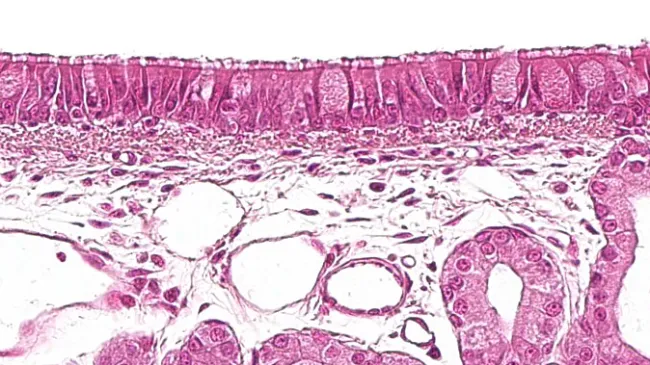

NEW SECTION OF THE NECROPSY MANUALIn this last installment of the manual, we detail some interesting aspects for collecting blood or blood clots, saliva, histopathological samples, exudates, and fecal and urine samples.

NEW SECTION OF THE NECROPSY MANUALIn this session, learn to examine the stomach, intestines, spleen, liver, kidneys, bladder, and reproductive organs. We'll explore enteritis, nephritis, cystitis, and more, finishing with the nervous system.